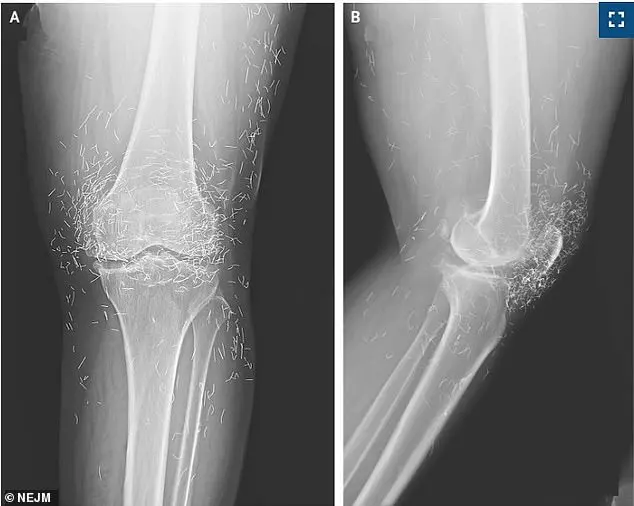

A 65-year-old woman in South Korea, seeking relief from osteoarthritis pain through alternative medicine, was left in shock when an X-ray revealed hundreds of gold threads embedded in her knees.

Doctors treating the woman, whose case was detailed in the *New England Journal of Medicine*, emphasized the diagnostic challenges posed by the threads.

On imaging, the specks clustered around her kneecaps and extended toward her shin and thigh, obscuring critical anatomical details. 'This case underscores a growing concern,' said one physician involved in the report. 'Alternative therapies like gold thread acupuncture can complicate medical imaging and delay proper diagnosis, especially when symptoms worsen unexpectedly.' The medical team did not specify whether the threads were removed, but experts warn that leaving them in place can lead to severe complications, including infections and organ damage if the threads migrate.